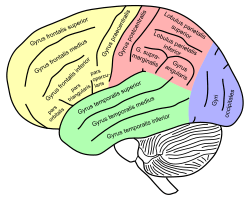

Inferior frontal gyrus of the human brain, gyrus frontalis inferior. | |

Lateral surface of left cerebral hemisphere, viewed from the side. | |

The inferior frontal gyrus is a gyrus of the frontal lobe (the yellow area of the human brain image to the right). It is labelled gyrus frontalis inferior, its Latin name. In the yellow area, its superior border is the inferior frontal sulcus (which divides it from the gyrus frontalis medius in the yellow area), its inferior border the lateral fissure (which divides it from the gyrus temporalis superior in the green area), and its posterior border is the inferior precentral sulcus (in the yellow area). Above it is the middle frontal gyrus (the gyrus frontalis medius), behind it the precentral gyrus (the gyrus praecentralis), both gyri in the yellow area of the image.[1]

The inferior frontal gyrus can be subdivided into the following macroanatomical structures, shown in yellow in the top image, just below the label gyrus frontalis inferior:

Drawing to illustrate the relations of the brain to the skull. Lateral view of a human brain, main gyri labeled.

Lateral view of a human brain, main gyri labeled.- Human brain - left and right hemispheres - superior-lateral view: Inferior frontal gyrus is labelled 6